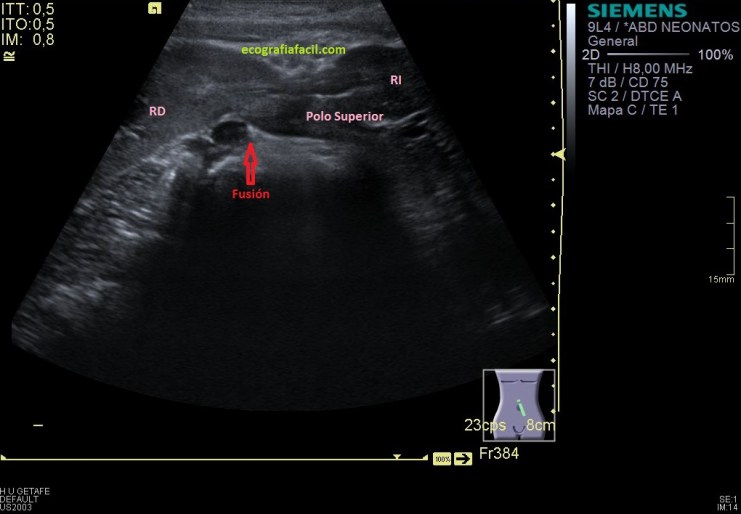

En este caso concreto hacemos seguimiento de una ectopia renal cruzada, figura que es variante de la ectopia renal, que puede ser simple o cruzada, que a su vez, si es cruzada, puede ser con o sin fusión con el riñón contralateral.

Y nos quedaba buscar el polo superior, imagen 8, buscándolo nos encontramos que este polo superior está unido al polo inferior del RD, sí lo sabía, pero el protocolo de búsqueda de ambos polos renales individualizadamente te garantiza que este tipo de malformaciónes, tipo riñón en herradura, no se escapen. En este caso se ve fenomenal, como ambos polos están, unidos entre sí